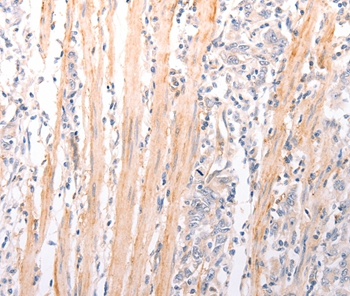

Immunohistochemical analysis of paraffin-embedded Human cervical cancer tissue using #37304 at dilution 1/50.

Immunohistochemical analysis of paraffin-embedded Human gastric cancer tissue using #37304 at dilution 1/50.